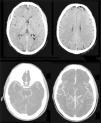

Caso clÃnicoUn paciente masculino de 57años de edad, sin otro factor de riesgo cardiovascular que ex-tabaquismo (22paquetes/año, suspendiendo 14años atrás), ingresa a nuestra institución presentando un cuadro de 45min de evolución consistente en disartria severa, paresia facial derecha severa y paresia braquicrural derecha leve. La primera evaluación médica fue realizada por profesionales de la guardia de emergencias, quienes refirieron que el paciente padecÃa afasia. Veinte minutos tras su ingreso, el puntaje de ictus del NIHSS evaluado por un neurólogo era de 6 (disartria 2 puntos, paresia facial 2, paresia braquial 1, paresia crural 1). La presión arterial (PA) de ingreso fue de 150/90. Con 60min de evolución se realizó una tomografÃa cerebral (TC) con angiotomografÃa (ATC) cerebral (fig. 1) y de vasos de cuello que no demostró sangrado ni lesión isquémica evidente, logrando un puntaje de Alberta Stroke Programe Early CT Score (ASPECTS)1 de 10. En la ATC cerebral no se observó obstrucción, y el puntaje Collateral Score2 fue de 3. En la ATC de vasos de cuello no se observaron estenosis ni lesiones ateroscleróticas. Una reevaluación realizada a las 1:30h de evolución constató una mejorÃa espontánea del cuadro clÃnico, con una reducción de NIHSS a 3 (disartria moderada 1, paresia facial moderada 1, paresia braquial derecha leve 1) en contexto de PA 150/80. Como parte del protocolo de atención, el paciente contaba con dos vÃas periféricas antebraquiales (una en cada brazo) con un goteo lento de solución fisiológica para asegurar su permeabilidad. En ese momento, familiares acompañantes refirieron que minutos antes de la evaluación se hallaba completamente asintomático sin déficit para ellos evidente. Ante tal revelación, llevando 2h de evolución, se realiza maniobra de Trendelenburg y apertura de la infusión de solución fisiológica «a chorro», elevándose la PA a 170/90 y desapareciendo todo déficit neurológico. Media hora después, al agotarse los reservorios de solución fisiológica, y aunque permanecÃa en posición de Trendelenburg, el cuadro deteriora nuevamente volviendo al estado clÃnico inmediatamente anterior con NIHSS de 3, esta vez en contexto de PA 160/80. Se repone infusión de solución fisiológica y el cuadro nuevamente evoluciona favorablemente con NIHSS de 0 y PA de 176/90. El paciente permanece en monitoreo estricto y clÃnicamente estable hasta cumplidas las 3h de evolución, donde a pesar de infusión de solución salina y posición de Trendelenburg la presión arterial desciende a 160/90 y el NIHSS deteriora a 3, presentando siempre el mismo déficit clÃnico (disartria leve-moderada, paresia derecha facial moderada, paresia braquial derecha moderada). Considerando la posibilidad de una trombosis suboclusiva de pequeña arteria con perfusión de miseria (dependiente de PA elevada), se decidió iniciar infusión de Alteplase (dosis plena total 72mg, 10% en bolo endovenoso y el 90% restante en infusión continua a lo largo de una hora). Durante la infusión la PA osciló entre 165 y 158 (sistólica) y 90 a 86 (diastólica). Durante toda la infusión el paciente permaneció en decúbito dorsal a 0 grados respecto al suelo. La evaluación secuencial de NIHSS fue: 3 puntos (basal), 2 puntos (15min de infusión), 0 puntos (30 y 45min de infusión). Al final de la infusión, con PA 160/80, se objetiva nueva fluctuación del cuadro clÃnico, presentando nuevamente NIHSS de 3. A pesar de que el cuadro clÃnico sugerÃa una topografÃa lacunar, dado que al ingreso del paciente el médico que le recibe refirió que el paciente presentaba afasia, ante la posibilidad de estenosis de ramas distales de la arteria cerebral media izquierda se decide realizar angiografÃa digital en busca de estenosis, procedimiento realizado a las 5h 30min, descartando con dicho estudio la presencia de estenosis silviana proximal y distal. Finalizada la angiografÃa digital, se constata que el paciente presentaba un NIHSS de 0 puntos. Por último, desde la sala de hemodinamia fue trasladado para la realización de un protocolo corto de resonancia (secuencias FLAIR, susceptibilidad magnética, difusión y ADC) donde se apreció una lesión isquémica aguda en topografÃa lenticulocapsular izquierda de 26mm de diámetro máximo con restricción de la difusión, ya visible nÃtidamente en secuencia FLAIR, y sin sangrados según susceptibilidad magnética (fig. 2); la RM fue realizada habiendo transcurrido 6h y 40min desde el inicio del cuadro. El paciente ingresó a la unidad de cuidados crÃticos a las 7h de evolución para continuidad de su atención y monitoreo. Se logró estabilizar la presión mediante infusión de solución fisiológica e infusión continua de noradrenalina. A las 24h, sin mediar complicación alguna ni fluctuaciones en presión arterial, el paciente presentaba un NIHSS de 3 (disartria leve, paresia facial central derecha leve, paresia del miembro superior derecho leve). La TC realizada a las 24h post-trombólisis como control rutinario (fig. 3) demostró la presencia de una lesión hipodensa lenticulocapsular izquierda en idéntica topografÃa a la evidenciada en la resonancia magnética, y no se observaron lesiones compatibles con sangrado. Durante la internación se realizó un ecocardiograma transtorácico que informó diámetros, espesores y función del ventrÃculo izquierdo conservado, sin valvulopatÃas ni dilatación auricular izquierda. El alta fue otorgada tras cumplir 6dÃas de internación, y se indicó continuar en forma ambulatoria con ácido acetilsalicÃlico 100mg/dÃa, atorvastatina 20mg/dÃa y enalapril 5mg/dÃa. Su NIHSS al alta fue de 1 (por presentar solo disartria leve). Al mes del evento el paciente ya no presentaba disartria, su NIHSS era de 0 y su puntaje en la escala modificada de Rankin era 0. Se solicitó un monitoreo Holter ambulatorio, pero el paciente no retornó a consulta posteriormente.